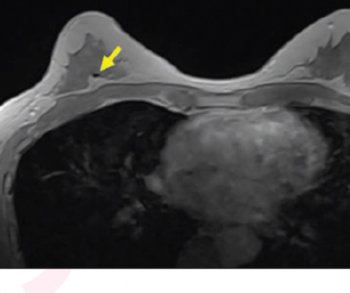

Emerging research suggests that the contrast-enhanced, in-phase Dixon sequence may be the most optimal sequence for detecting biopsy clips on breast magnetic resonance imaging (MRI).